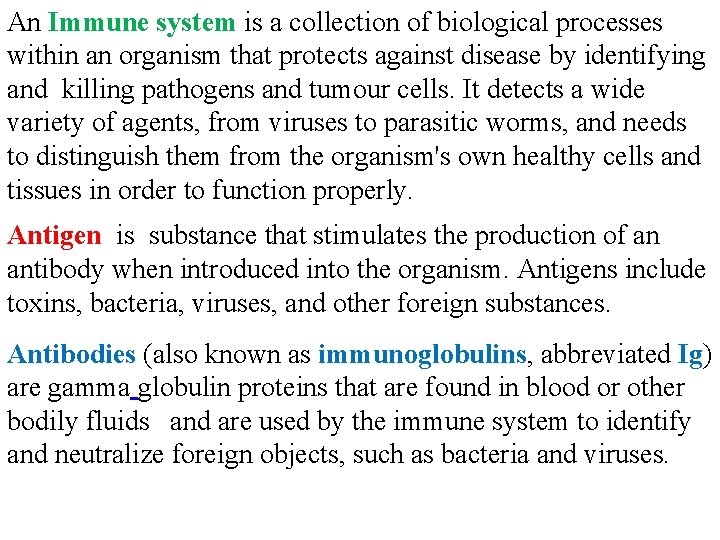

An Immune system is a collection of biological processes within an organism that protects against disease by identifying and killing pathogens and tumour cells. It detects a wide variety of agents, from viruses to parasitic worms, and needs to distinguish them from the organism's own healthy cells and tissues in order to function properly. Antigen is substance that stimulates the production of an antibody when introduced into the organism. Antigens include toxins, bacteria, viruses, and other foreign substances. Antibodies (also known as immunoglobulins, abbreviated Ig) are gamma globulin proteins that are found in blood or other bodily fluids and are used by the immune system to identify and neutralize foreign objects, such as bacteria and viruses.